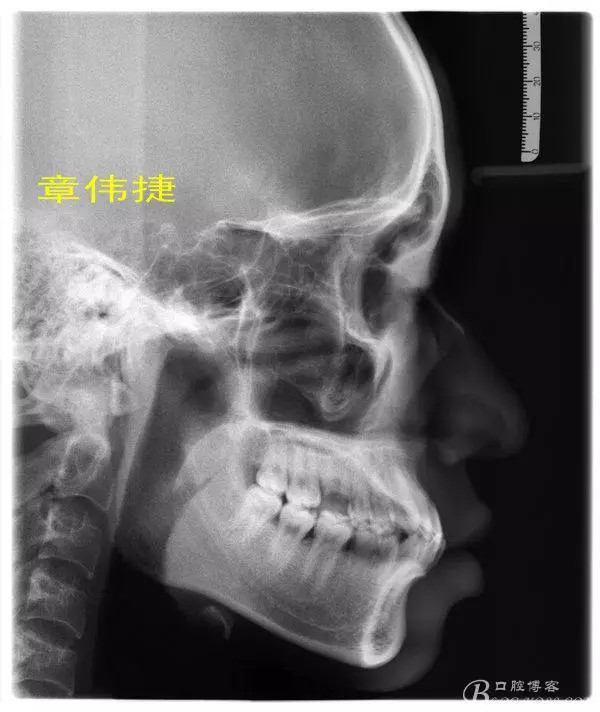

患者成年男性因下合牙間隙大,曾經(jīng)咨詢過多家醫(yī)院,建議修復(fù),但患者拒絕,來(lái)萬(wàn)眾口腔醫(yī)院正畸科就診。

術(shù)前資料: